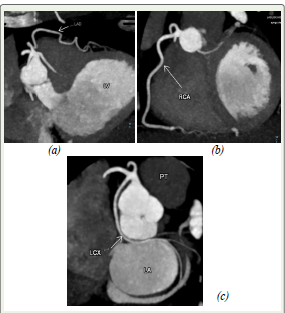

Figure 3: (a) shows a 3D volume-rendered image (VR) showing the origin of

all four vessels from a single trunk at the right coronary sinus. The dominant

RI branch is prominently visualized heading toward the anterolateral left

ventricular wall. (b) reveals the same findings after subtraction of the right

ventricle and it’s outflow tract. (c) Image highlighting the Obtuse Marginal

(OM) arteries arising from the LCx , which are small in caliber compared to

the prominent ramus intermedus (RI).

Abbreviations: VR – volume rendered; RI – ramus intermedius; RCA – right

coronary artery; LAD – left anterior descending artery; LCx – left circumflex

artery; AR- Aortic Root; LA- left atrium; PT - pulmonary trunk; OM- Ontuse

Marginal Artery

Figure 5: This Figure outlines the reformatted oblique CT angiographic

images showing the course of the other major coronary vessels, namely (a)

LAD (b) RCA (c) Lcx

Abbreviations: RCA – right coronary artery; LAD – left anterior descending

artery; LCx – left circumflex artery; LV- left ventricle; PT- pulmonary trunk;

LA- left atrium.